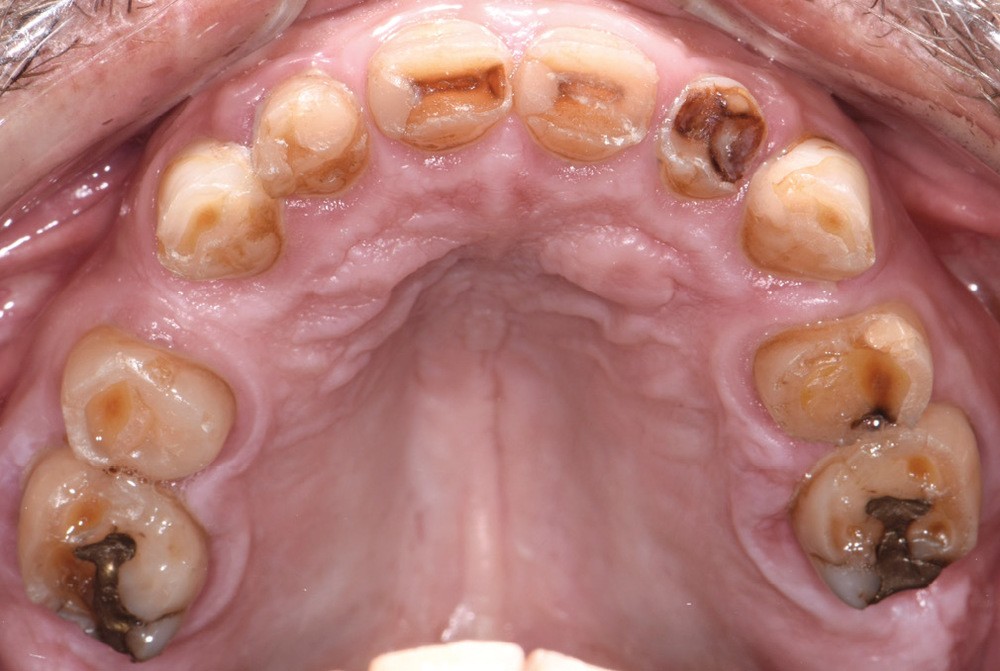

Au vu du contexte para-fonctionnel et de l’étendue de la perte tissulaire, des coiffes périphériques minimalement invasives ont été choisies afin de restaurer l’esthétique et la fonction. Actuellement, aucun consensus n’est fait sur le choix du matériau d’infrastructure à privilégier. Les matériaux hybrides usinables présentent des propriétés mécaniques, physiques et biologiques intéressantes en contexte d’usure sévère (e.g., module d’élasticité, résistance à la propagation de fêlures, facilité de réintervention). Une réhabilitation globale avec remontée de dimension verticale d’occlusion (DVO) par l’intermédiaire de coiffes composites renforcés en nano-céramiques est décrite.